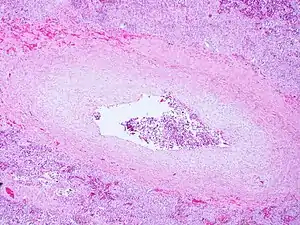

| Pulmonary veno-occlusive disease-Intimal fibrosis with marked narrowing of lumen of a large pulmonary vein | |

Pulmonary veno-occlusive disease may have a genetic basis. Published reports have indicated fatal occurrences that appeared to possess a familial pattern, more to the point, a germline mutation.[7] The pathophysiology of veno-occlusive disease culminates in occlusion of the pulmonary blood vessels. This could be due to edematous tissue (sclerotic fibrous tissue). Thickening is identified in lobular septal veins, also dilatation of lymphatics happens. Furthermore, alveolar capillaries become dilated (due to back-pressure).[8]